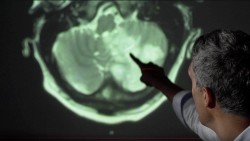

Efectele Covid-19 asupra creierului

Proteina spike a virusului SARS-CoV-2 poate trece prin bariera hematoencefalică a șoarecilor. Aceasta produce eliberarea de citokine de către creier, care are ca efect o inflamație a acestuia.

Virusul SARS-CoV-2, ca și alte virusuri dinaintea lui, reprezintă o amenințare pentru creier.

Medical, inflamația intensă cauzată de infecția COVID-19 este numită furtună de citokine. Sistemul imunitar, în momentul detectării virusului și a proteinelor sale, reacționează exagerat în încercarea sa de a distruge intrusul. Astfel, în urma inflamației creierului, persoana infectată rămâne cu ceață mintală, oboseală și alte probleme cognitive.